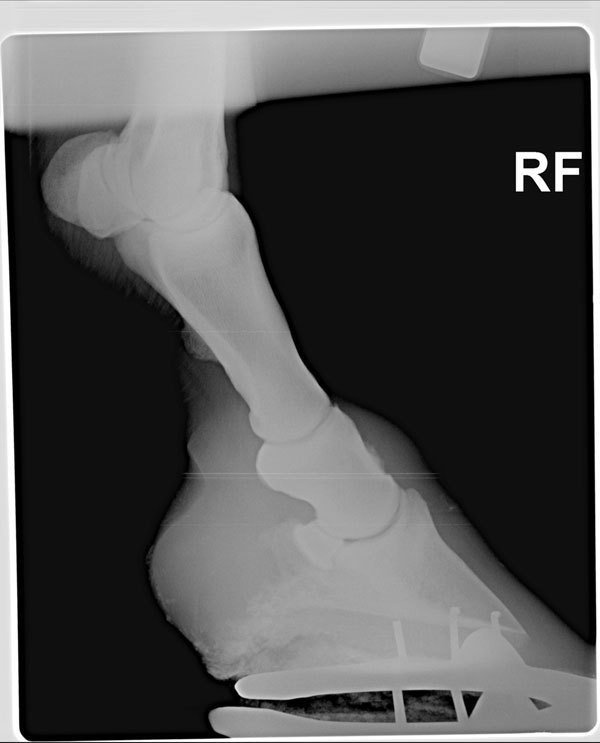

I have attached radiographs of my 16 year old gelding's right front pastern. He has been slightly lame for a month or so. We are trying to determine the treatment that would be best for him. I am alarmed at the bone spurs he has! I am trying to decide what course of action to take. We changed his shoes to increase ease of breakover and added pads. That has helped a lot. He seems better unless he is on very uneven ground or he makes a very sharp right turn. He is on Cosequin ASU and has been for some time. We are going to start Adequan IM and we are debating wether to do IRAP injections or HA injections. This gelding was also recently diagnosed with Cushingoid synDrOme and is on a very low dose of pergolide. He is my problem child at the moment!

Though there are signs of DJD in the pastern joint and remarkable bony proliferation in the bones of the pastern it is not clearly a cause of lameness. You may occasionally find horses with changes above in sound horses. However in combination with the results of the nerve blocks this is pretty damning. Is the history and clinical course of the lameness also consistent with a chronic, progressive disease that worsens with exercise?